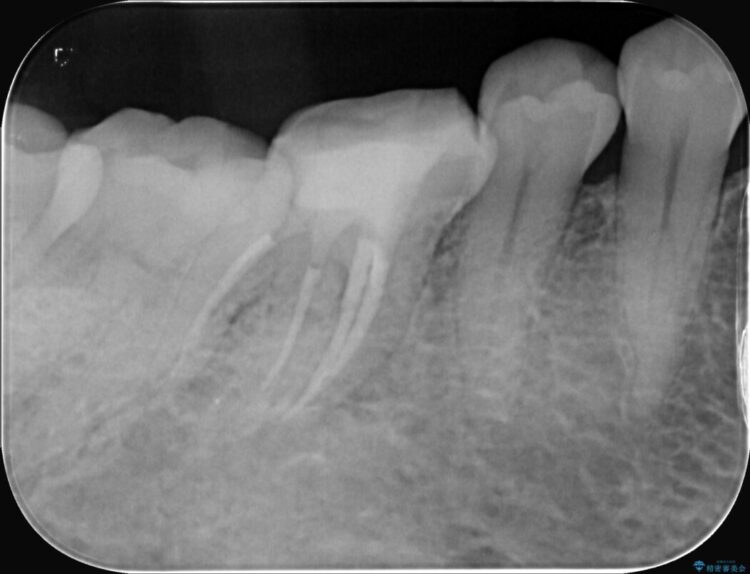

精密検査の結果、根の先に大きな病変が認められますが、根管内が狭窄し湾曲しているため、非常に難易度の高いケースです。

次に、根のカーブに沿ってしなやかに曲がるニッケルチタンファイルを使い、根の先まで徹底的に洗浄・殺菌を行いました。汚れを完全に取り除いた後、隙間なくお薬を詰めて密閉しています。

術後の経過は非常に良く、あんなに大きかった膿の袋は消え、健康な骨が再生しているのが確認できました。痛みや腫れも消えて抜歯を免れ、現在は被せ物を入れてしっかりお食事を楽しんでいただけるようになっています。